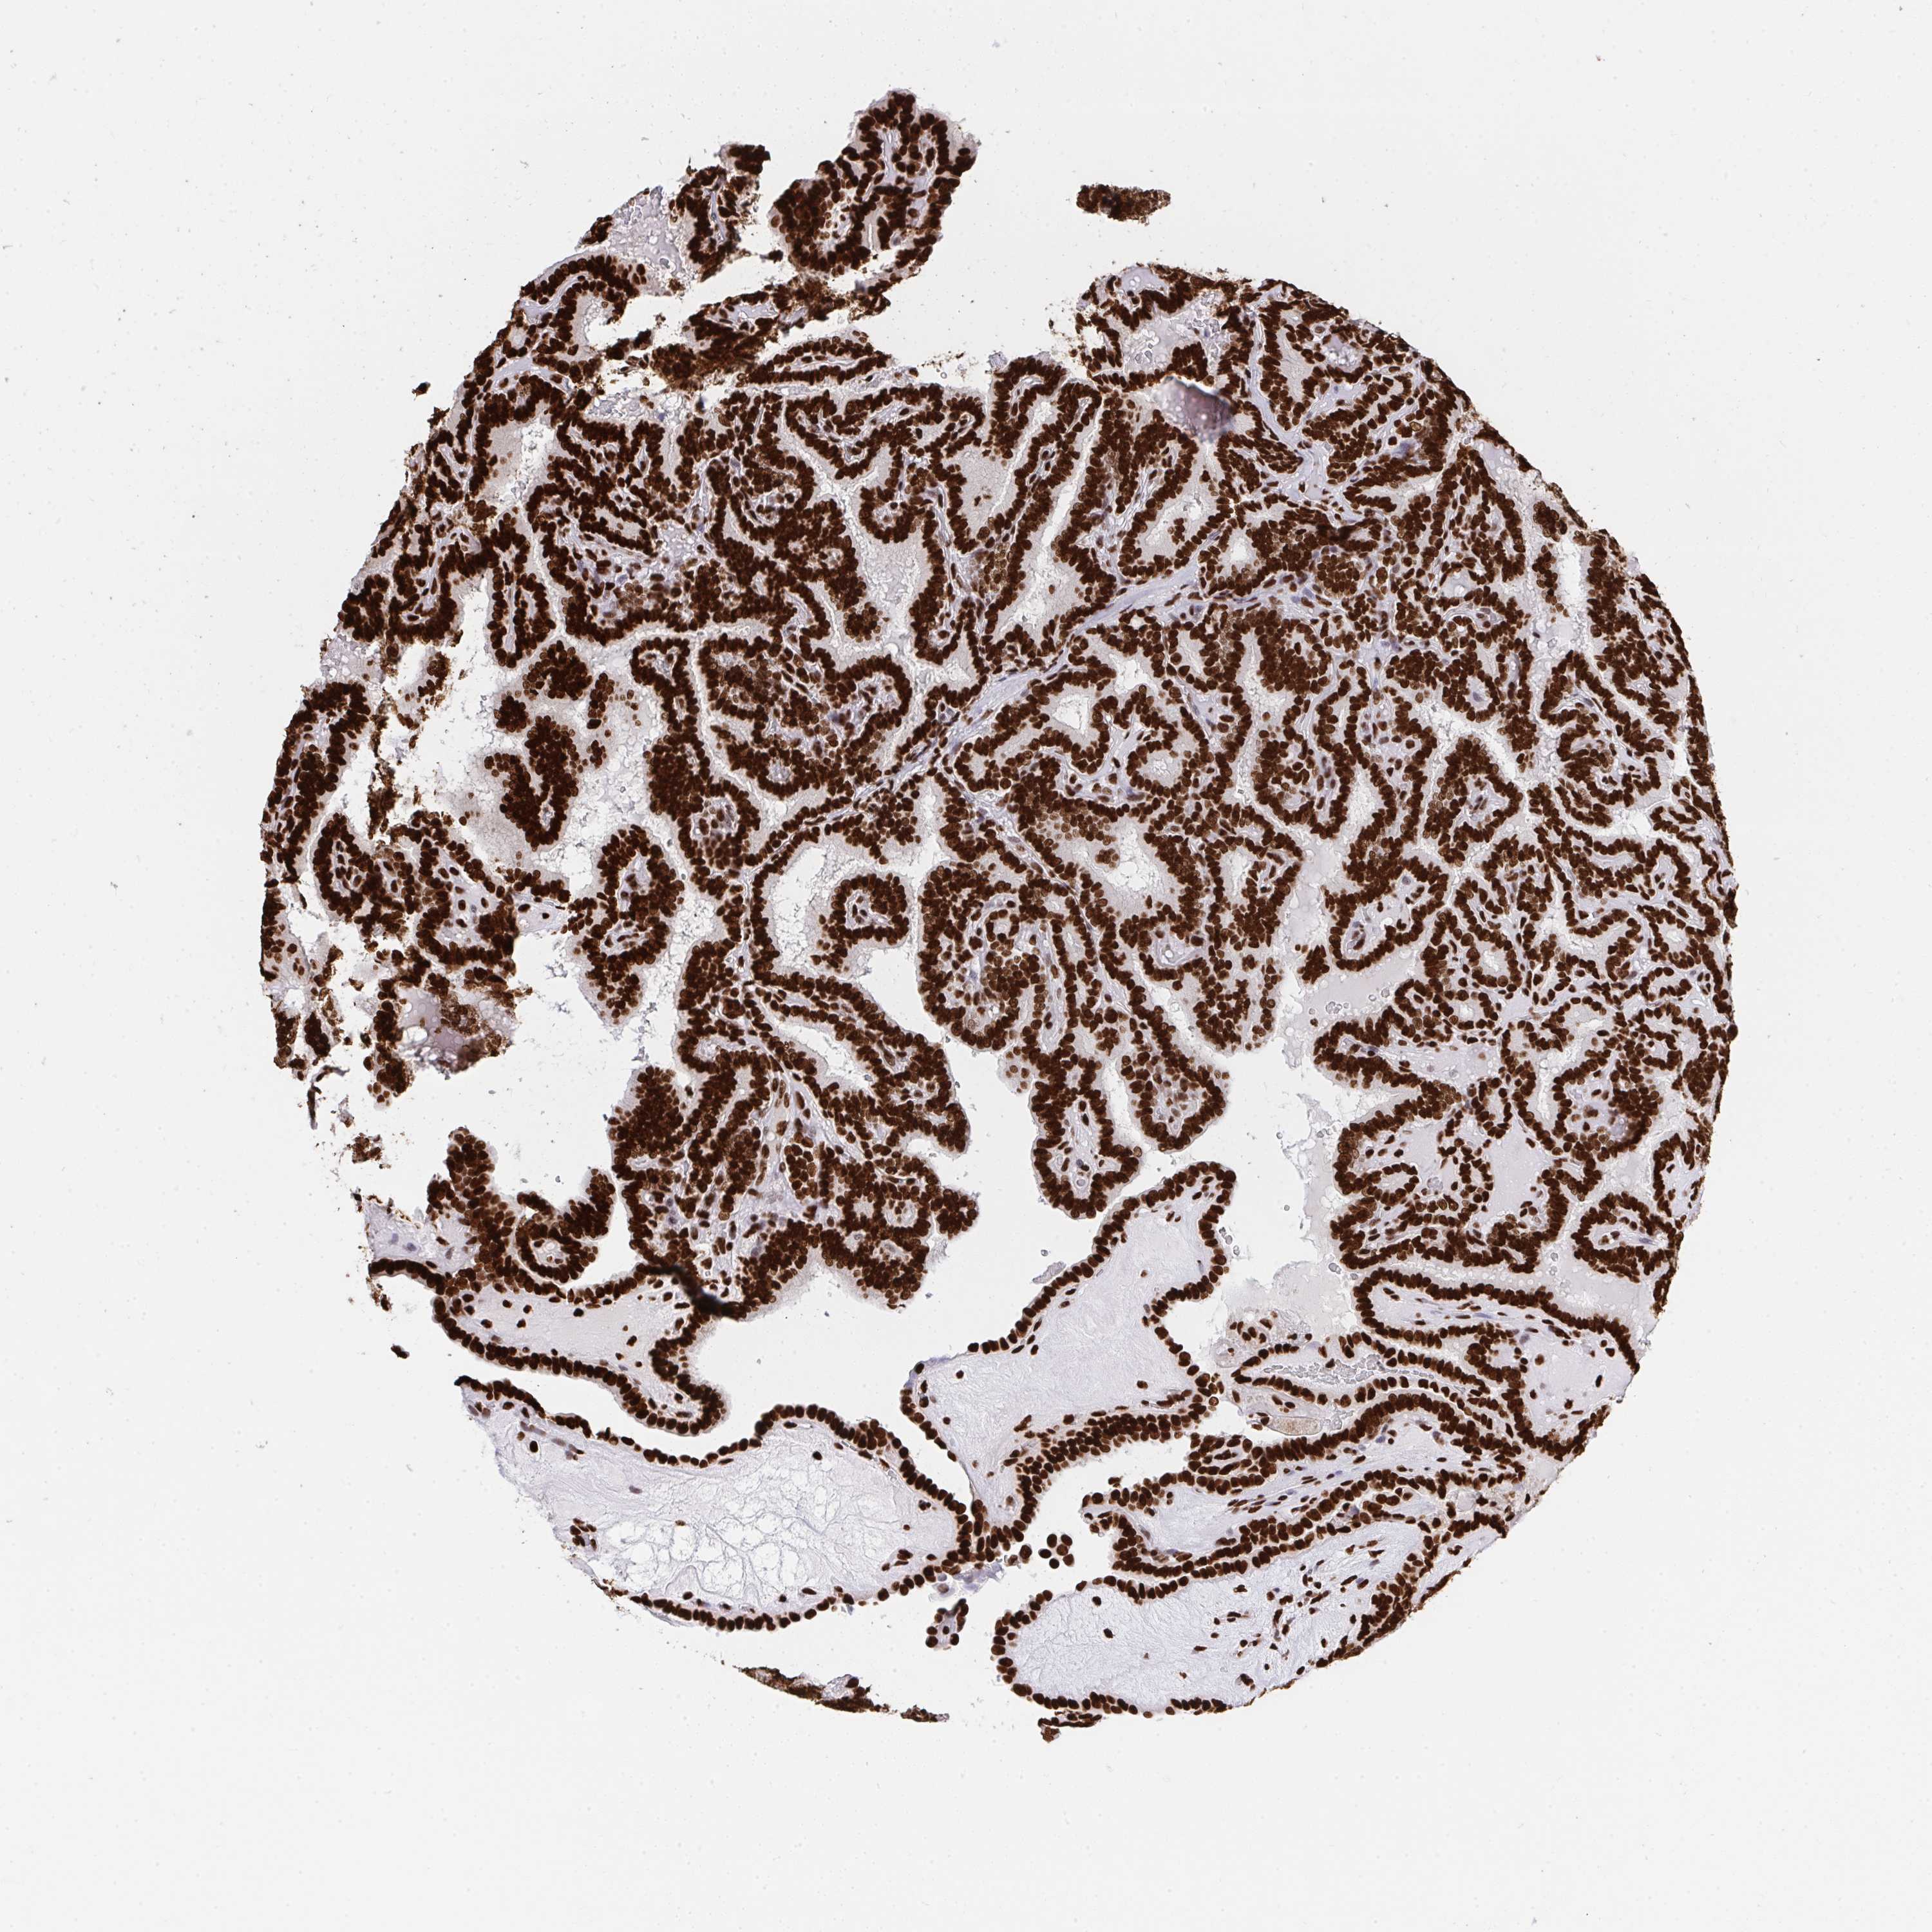

THYROID CANCER - Protein expressioni

A mouse-over function shows sample information and annotation data. Click on an image to view it in a full screen mode. Samples can be filtered based on level of antibody staining by selecting one or several of the following categories: high, medium, low and not detected. The assay and annotation is described here.

Note that samples used for immunohistochemistry by the Human Protein Atlas do not correspond to samples in the TCGA dataset.

Antibody stainingi

Antibody staining in the annotated cell types in the current human tissue is reported as not detected, low, medium, or high, based on conventional immunohistochemistry profiling in selected tissues. This score is based on the combination of the staining intensity and fraction of stained cells.

Each image is clickable and will lead to virtual microscopy that enables deeper exploration of all samples and also displays staining intensity scores, fraction scores and subcellular localization as well as patient and tissue information for each sample.

Antibody HPA051748

Antibody HPA052661

Antibody CAB016326

Staining

High

Medium

Low

Not detected

Intensity

Strong

Moderate

Weak

Negative

Quantity

>75%

75%-25%

<25%

None

Location

Nuclear

Cytoplasmic/membranous

Cytoplasmic/membranous,nuclear

Papillary adenocarcinoma, NOS

Follicular adenoma carcinoma, NOS